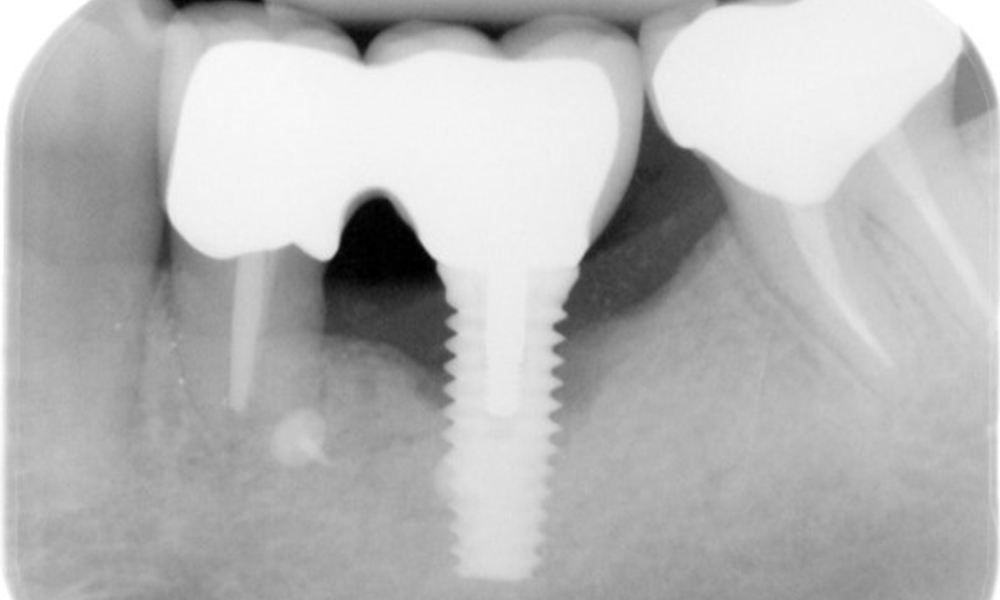

The X-ray images show the progression of bone loss.

The X-ray images show the progression of bone loss in the area of the implant in region 36: dental film from 11.02.2021 (left) and dental film from 18.01.2024 (right).